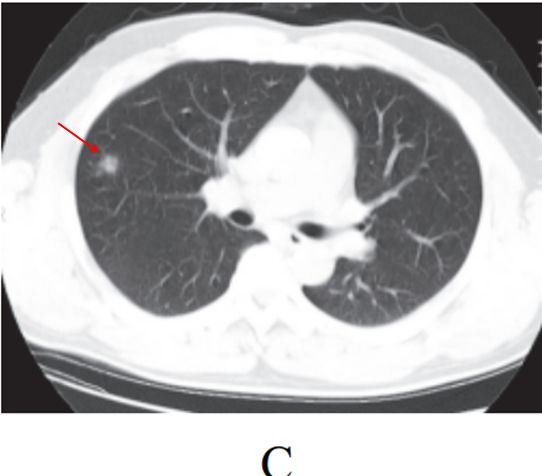

孤立性类圆形病灶(图 2-2C)

图片